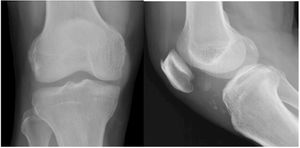

Case History: 20-year-old female with mild pain in left knee joint area, no history of injury and laboratory test was normal for inflammation or rheumatoid.